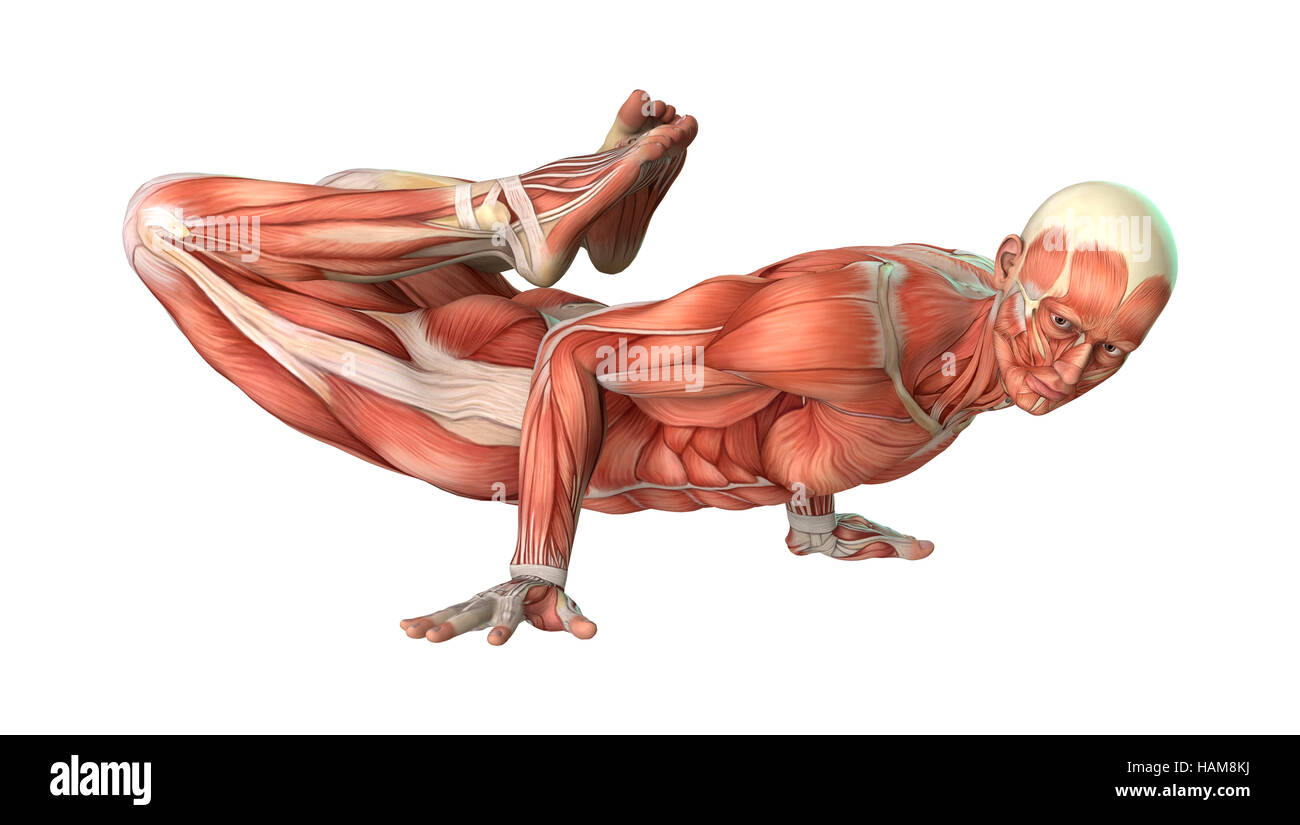

RFHAM8KJ–3D-Rendering einer männlichen Anatomie-Figur mit Muskeln Karte isolierten auf weißen Hintergrund